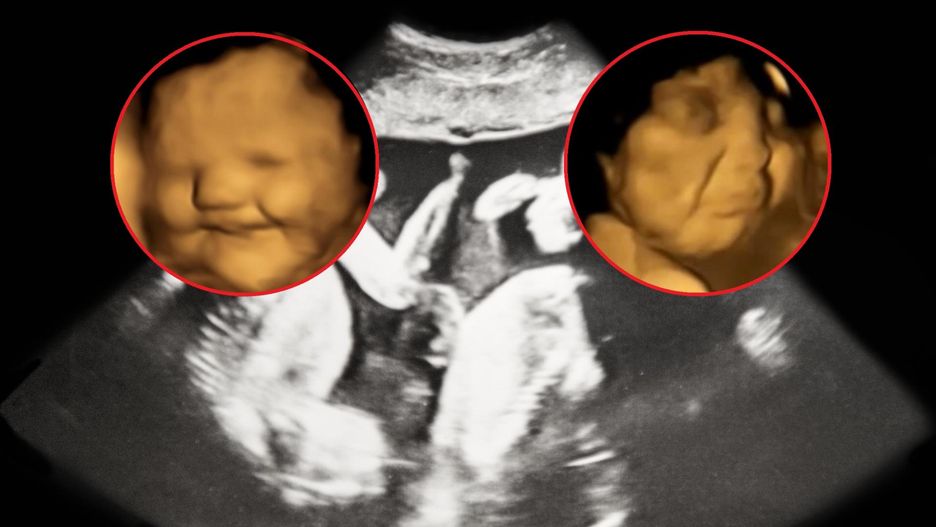

W tym celu przeprowadzili badania USG u 100 kobiet w ciąży, sprawdzając reakcje płodu na jedzone przez mamę potrawy. Zespół badał matki w wieku od 18 do 40 lat w 32. i 36. tygodniu ciąży. Wnioski były zaskakujące!

Naukowcy podali przyszłym mamom marchewkę i jarmuż. Następnie obserwowali, jak płody reagowały na ich smak.

Naukowcy dostrzegli na zdjęciach, że gdy do maluchów docierał smak marchewki, na ich buziach pokazywał się grymas przypominający uśmiech. Natomiast po wyczuciu smaku jarmużu, twarze nienarodzonych dzieci wykrzywiały się jak do płaczu.

Jak wyglądało samo badanie? Kobietom podawano jedną kapsułkę zawierającą około 400 mg marchewki lub 400 mg sproszkowanego jarmużu na około 20 minut przed każdym badaniem. Poproszono je, aby nie spożywały żadnych posiłków ani napojów smakowych na godzinę przed badaniem.

Reakcje nienarodzonych dzieci obserwowane w obu grupach (w porównaniu z tymi z grupy kontrolnej, które nie były narażone na żaden smak) wykazały, że ekspozycja na niewielką nawet ilość marchwi lub jarmużu wystarczyła do wywołania reakcji uśmiechu, lub płaczu.